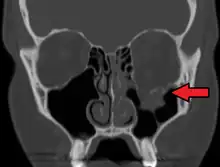

| An orbital blowout fracture of the floor of the left orbit. | |

An orbital blowout fracture is a traumatic deformity of the orbital floor or medial wall that typically results from the impact of a blunt object larger than the orbital aperture, or eye socket.[1] Most commonly this results in a herniation of orbital contents through the orbital fractures.[1] The proximity of maxillary and ethmoidal sinus increases the susceptibility of the floor and medial wall for the orbital blowout fracture in these anatomical sites.[2] Most commonly, the inferior orbital wall, or the floor, is likely to collapse, because the bones of the roof and lateral walls are robust.[2] Although the bone forming the medial wall is the thinnest, it is buttressed by the bone separating the ethmoidal air cells.[2] The comparatively thin bone of the floor of the orbit and roof of the maxillary sinus has no support and so the inferior wall collapses mostly. Therefore, medial wall blowout fractures are the second-most common, and superior wall, or roof and lateral wall, blowout fractures are uncommon and rare, respectively. They are characterized by double vision, sunken ocular globes, and loss of sensation of the cheek and upper gums from infraorbital nerve injury.[3]

Thin cut (2-3mm) CT scan with axial and coronal view is the optimal study of choice for orbital fractures.[16][17]